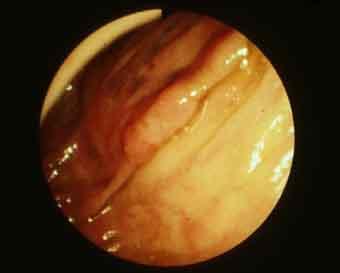

질환(병리주체)의 분류 악성 상피성종양/선암

부위(장기별) 대장/상행

검사방법 내시경

종양의 육안분류 0형(표재형)/IIa형(IIa)

종양의 최대경(밀리미터) 10~14

종양의 심달도 m